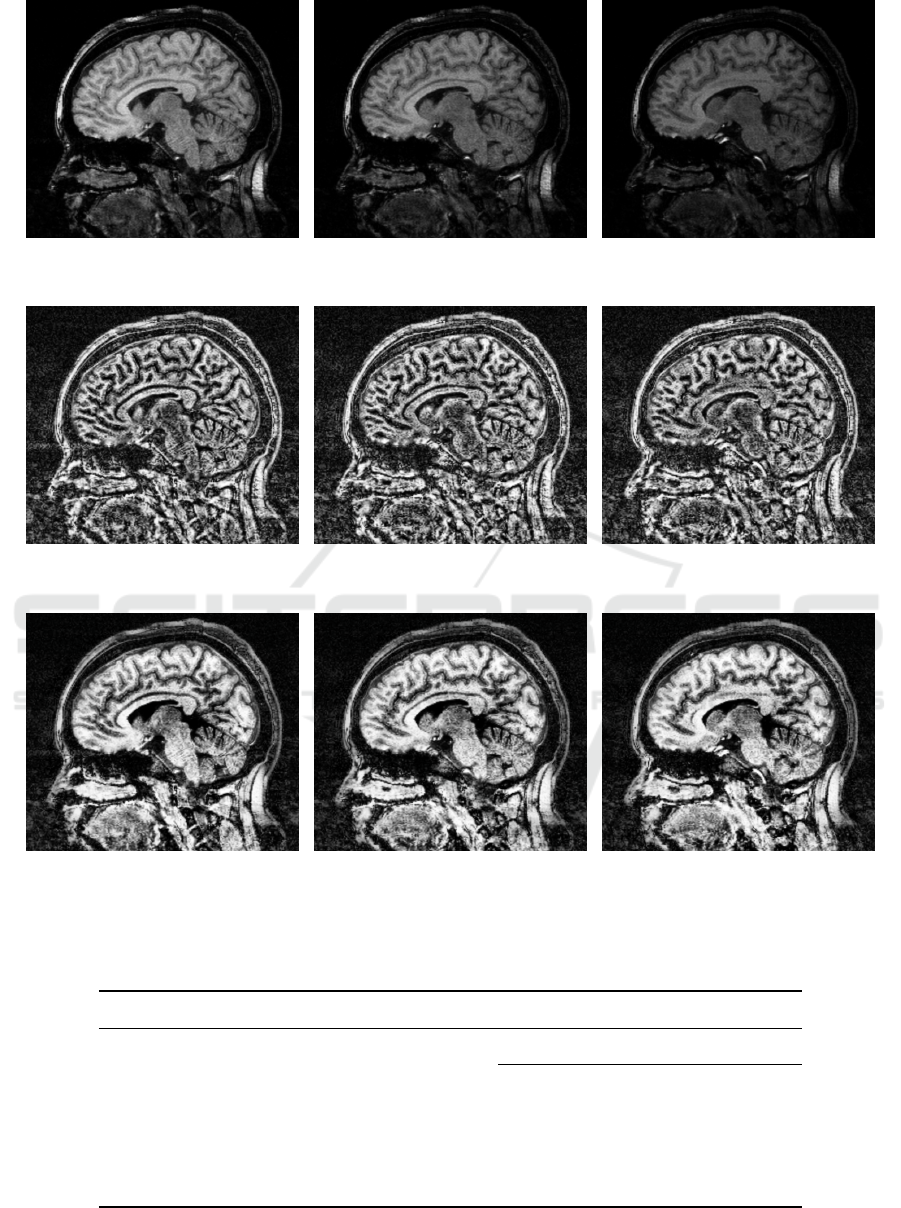

Marcus, D., Wang, T., Parker, J., Csernansky, J., Morris, J.,

and Buckner, R. (2007). Open Access Series of Imag-

ing Studies (OASIS): Cross-Sectional MRI Data in

Young, Middle Aged, Nondemented, and Demented

Older Adults. Journal of Cognitive Neuroscience,

19(9):1498–1507.